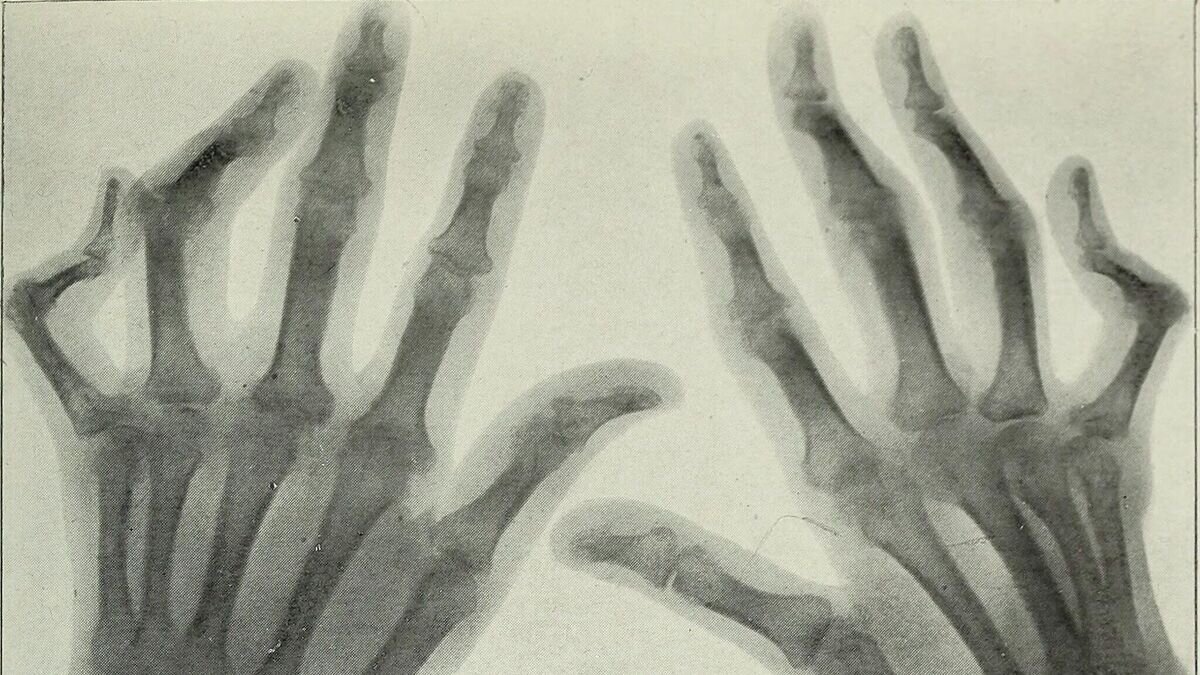

Руки человека, пораженного артритомCC0 / Internet Archive Book Images /

Один из характерных симптомов ревматоидного артрита – симметричное поражение мелких суставов пальцев и кисти, но иногда заболевание может начаться с поражения крупных суставов, например коленного или плечевого. Течение сопровождается сменой обострений и ремиссий, по мере развития артрита суставы разрушаются, соединительная ткань разрастается, что приводит к вывихам и подвывихам, а далее к инвалидизации.